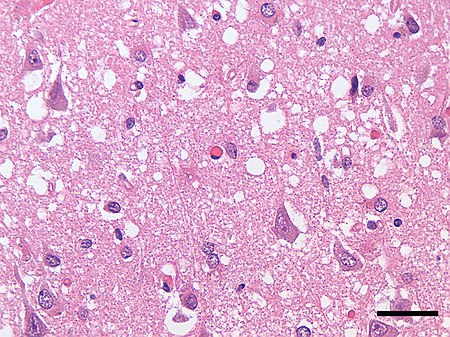

Ο βιολόγος ιολόγος Λικ Μοντανιέ (18/02/1932-08/02/2022) είχε ανακαλύψει τον ίο του AIDS(HIV) βραβευμένος με νόμπελ ιατρικής (2008), σε συνέντευξη του στο sud radio 17/11/2021 ανέφερε κρούσματα της νόσου prion τύπου τρελών αγελάδων σε διαφορετικούς ανθρώπους που το μόνο κοινό πού είχαν ήταν ότι είχαν κάνει και τις δύο δόσεις του ιδίου ακριβώς υιικού εμβόλιού .

Το prion προκαλεί τρέλα καθώς εκφυλίζει τον εγκέφαλο δημιουργούνται άνοια , αστάθεια βαδίσματος και ισορροπίας ,σπασμούς , αλλαγή συμπεριφοράς η προσωπικότητας διαταραχή ομιλίας ως και απώλεια μνήμης , κατάθλιψη και παράνοια .